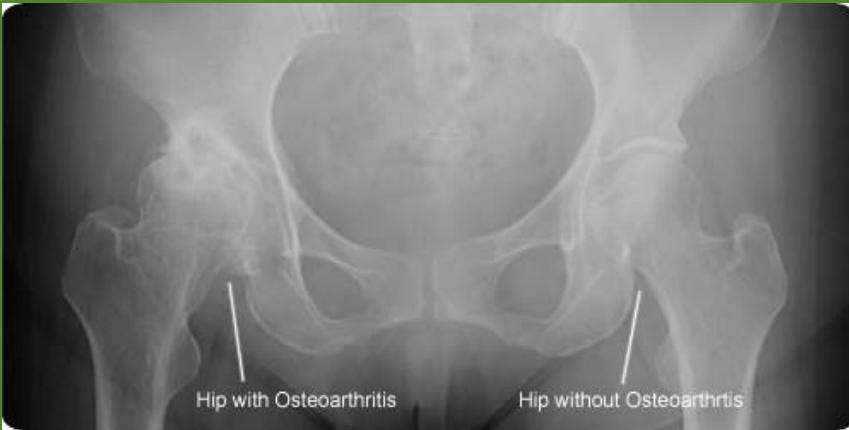

Examination of HIP

| Item | Procedure | Additional Information … | Attachments |

| Look | General statement on the patient | General Assessment: Patient’s overall condition and comfort level. Local hip-thigh-lower limb assessment: Position and alignment, major deformities and swelling, external devices (casts, splints, traction, dressings). Anatomical Local Assessment: Skin (swelling, scars, color, hair distribution, dryness), Subcutaneous tissue (lymph nodes, veins, nerves, tendons), Muscles (bulk, wasting, fasciculations), Bones (landmarks, swelling, angulation, deformity), Joints (position, swelling, redness). Important: Always examine the posterior aspect. | Normal Positioning![]() Left hip abnormal positioning ![]() Bilateral hip abnormal positioning ![]() Wheelchair positioning ![]() Local Hip-Thigh-Lower Limb Assessment (Position): Position assessment ![]() Postural Changes: Lumbar lordosis ![]() Major Deformities and Swelling: Major deformities ![]() Additional deformity examples ![]() More deformity examples ![]() External Devices (Immobilization): Cast example ![]() Additional cast examples ![]() More cast examples ![]() External Devices (Traction): Traction examples ![]() Additional traction examples ![]() More traction examples ![]() External Devices (Orthotics): Orthotics example 1 ![]() Orthotics example 2 ![]() |